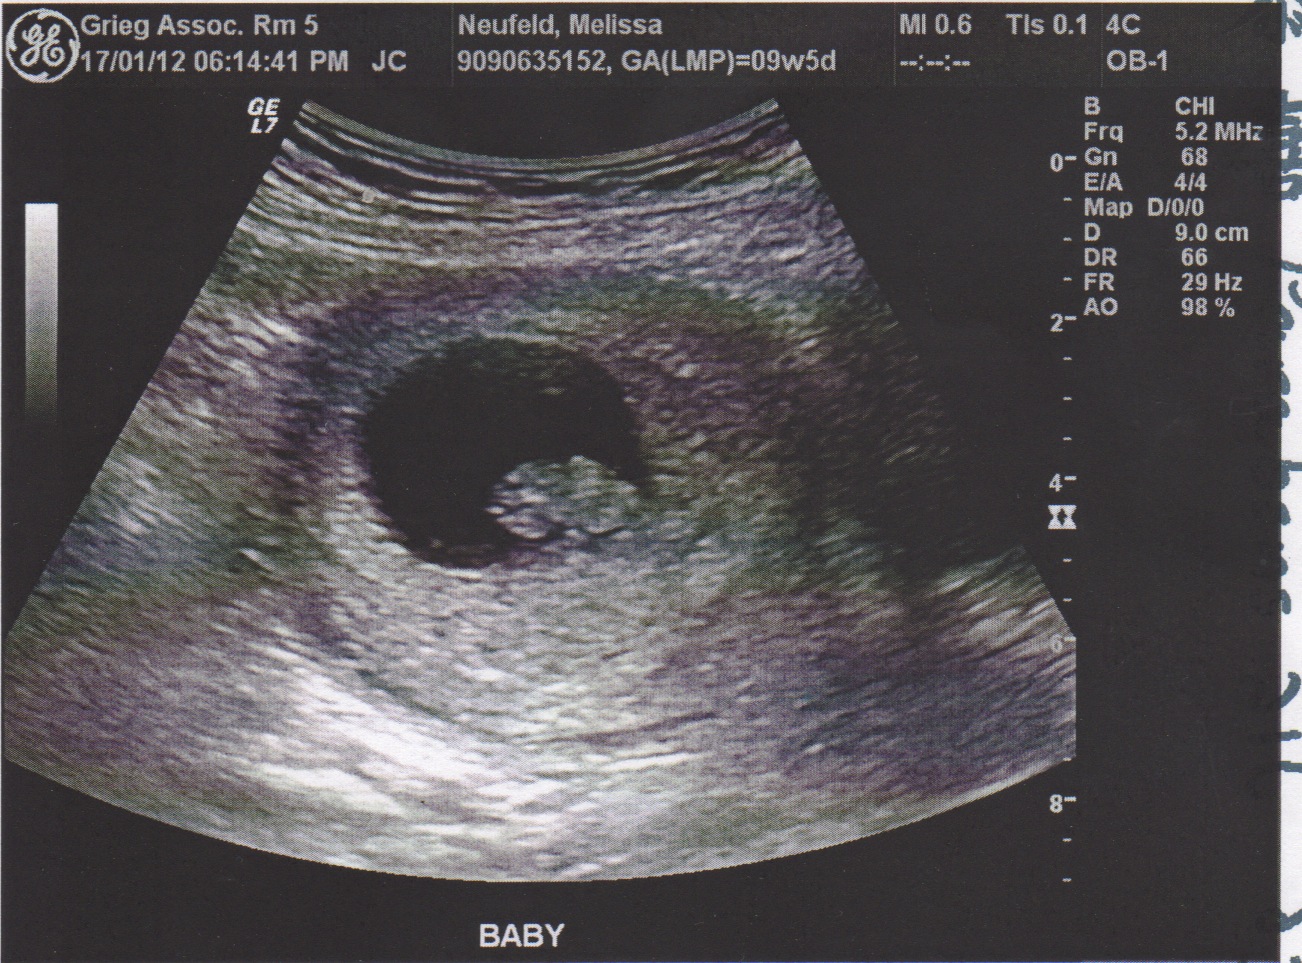

Узи 6 недель нет сердцебиения

Узи 6 недель нет сердцебиения 119 фотографий